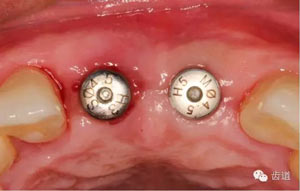

合面觀